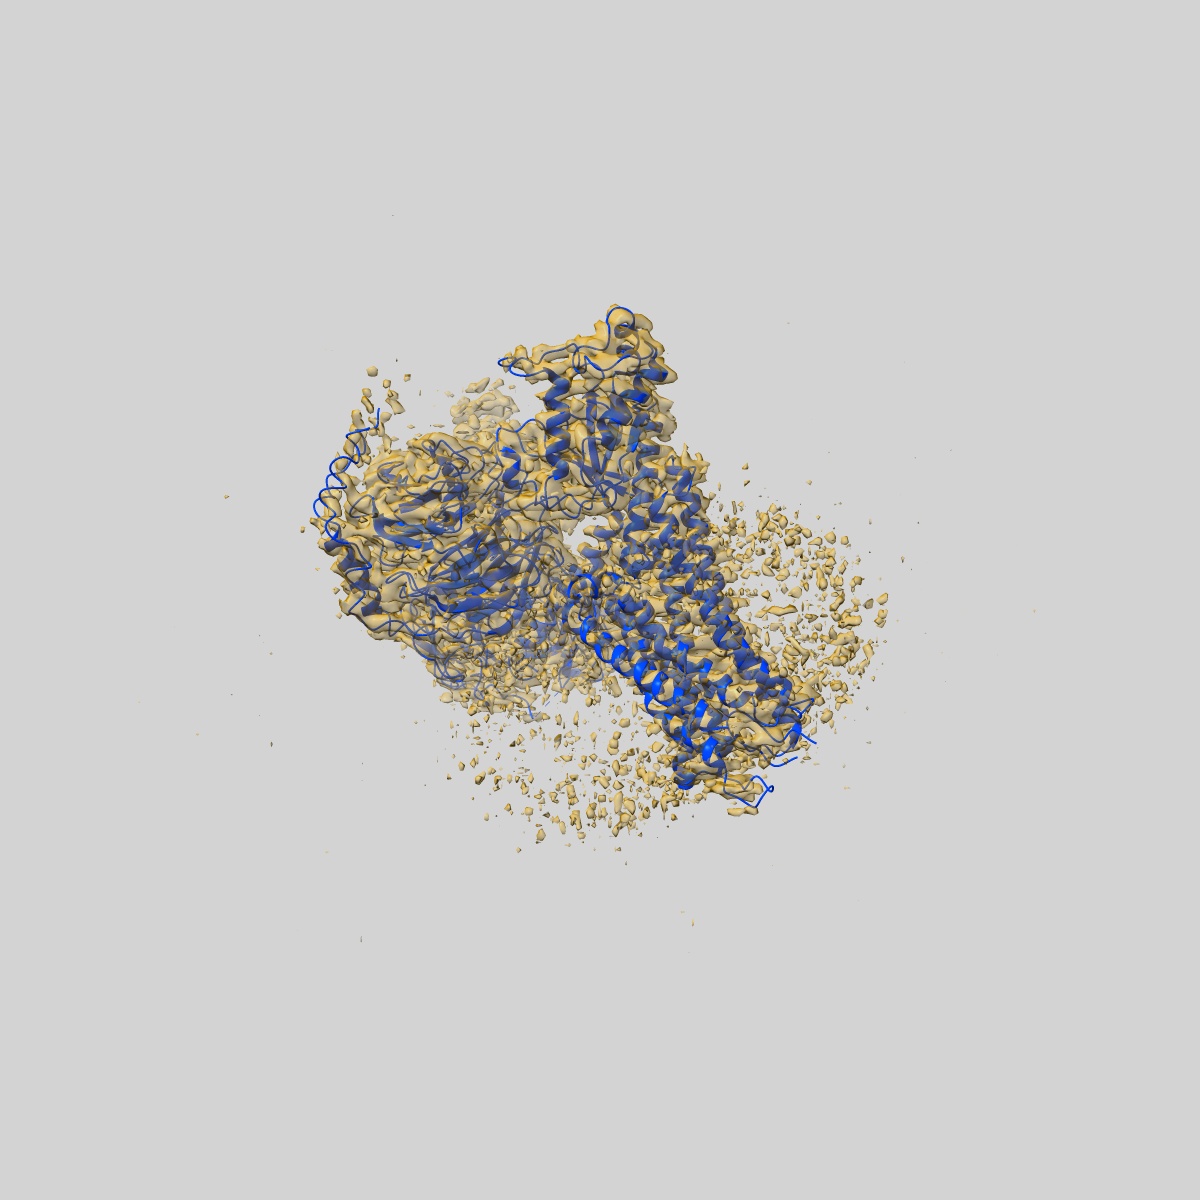

CryoEM structure of somatostatin receptor 4 (SSTR4) in complex with Gi1 and its endogeneous ligand SST-14

Sample: Complex structure of somatostatin receptor 4 (SSTR4) in complex with Gi and its endogeneous ligand SST-14

Fitted models: 7xms

Structural insights into ligand recognition and selectivity of somatostatin receptors.